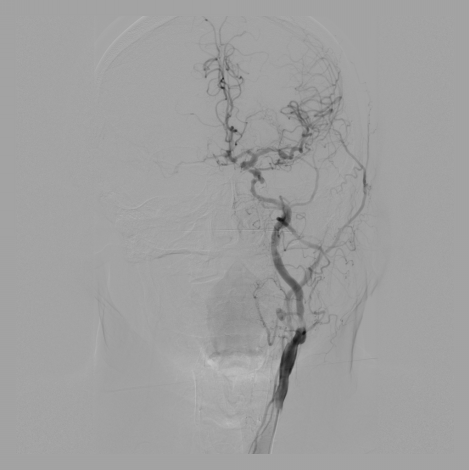

减影图像效果